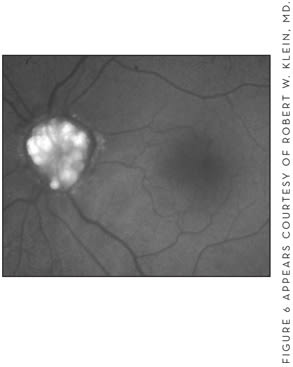

■ Autofluorescence. This is a noninvasive exam that characteristically shows the phenomenon of autofluorescence, most evident in exposed drusen (Figure 6).

Figure 6. This image of optic nerve drusen autofluorescence shows that these hyaline bodies are highly autofluorescent.